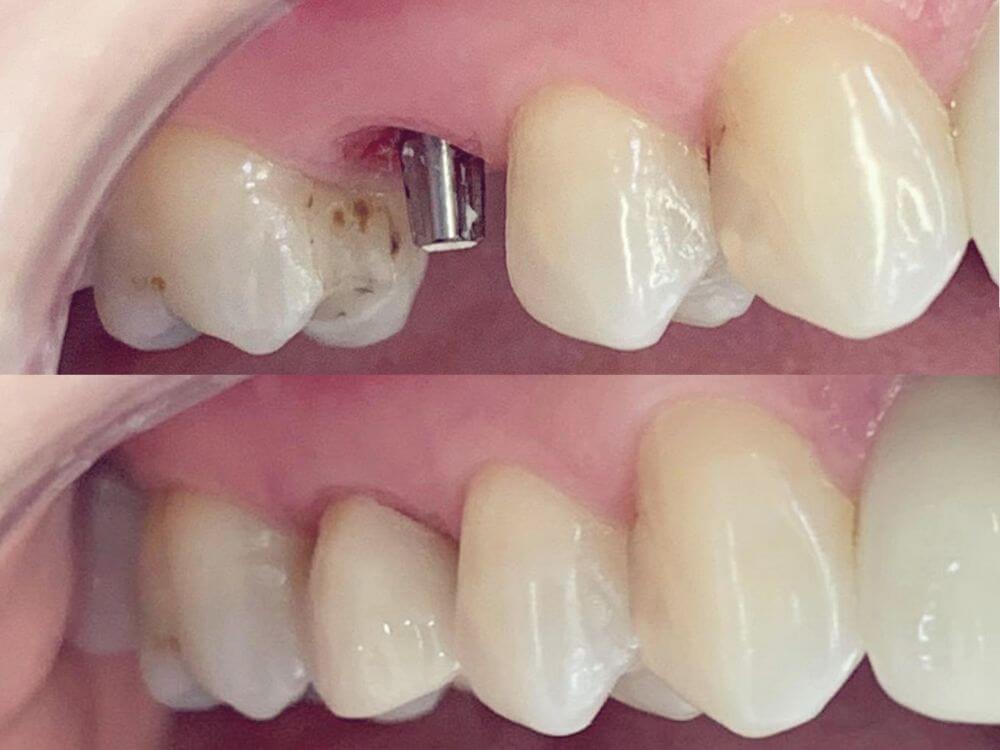

Implantes e a prótese são instalados no mesmo dia. Resultados estéticos e funcionais rápidos. Em até 72 horas, seu sorriso é completamente reconstruído.